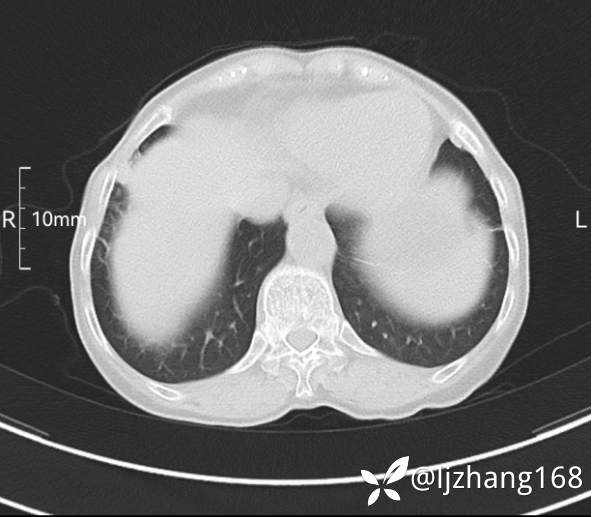

74岁女患,反复咳嗽2月,右肺空洞性病变,炎症OR肿瘤(有病理)

简要病史:2月前开始受凉后出现咳嗽,咳少许白色粘液痰,痰不易咳出,无痰中带血及咯血,无畏寒发热,外院胸部CT提示右下肺空洞病变,脓肿可能性大,常规抗感染治疗效果不佳。既往否认“糖尿病”等病史,有高血压基础病史,无吸烟史。

辅助检查:胸部CT右肺下叶前基底段结节并空洞

临床诊断:右肺空洞:脓肿?